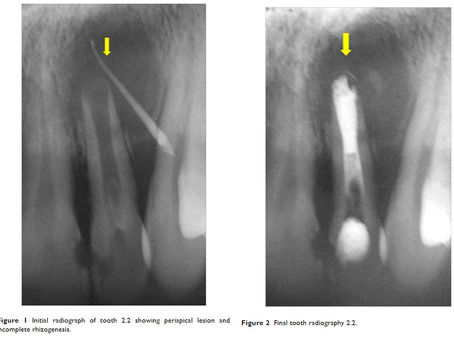

Casos clínicos

Explore nossos casos clínicos sobre o uso de cimento biocerâmico Cimmo: aplicações reais, abordagens práticas e resultados transformadores para inspirar e aprimorar sua prática odontológica.